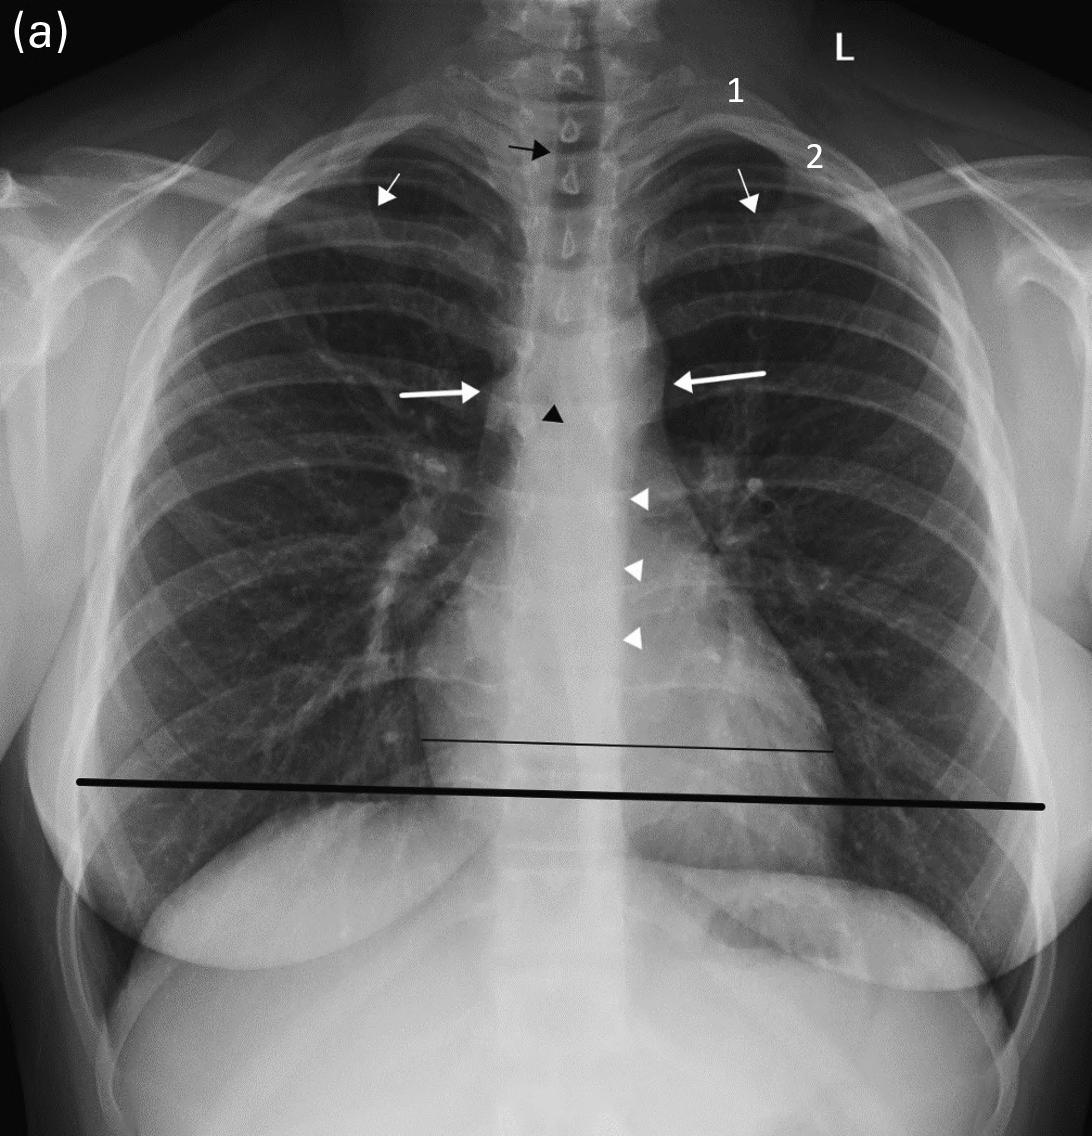

The clinicians for this patient started with a chest radiograph. The initial chest radiographic identified small pleural effusions and interlobular septal thickening, which were suggestive of interstitial pulmonary edema (see Figures 1.1a and 1.1b). Findings become more apparent when compared with a normal 16-year-old’s chest radiographs (Figures 1.2a and 1.2b). Because of the patient’s vomiting, an abdominal film was also obtained, which demonstrated significant cardiomegaly (see Figure 1.1c), thus leading to the diagnosis of dilated cardiomyopathy and/or pericardial effusion. On the chest radiograph, the reduced lung volumes and elevated hemidiaphragms masked the cardiomegaly, which was more apparent on the better penetrated abdominal radiograph.

FIGURES 1.1 a, 1.1b, 1.1c, AND 1.1d . (a, b) PA and lateral views of the chest demonstrating low lung volumes, pulmonary vascular congestion, interstitial opacities in the lung bases, and bilateral trace pleural fluid; (c) the abdominal radiograph is better penetrated than the chest radiograph, and shows an enlarged cardiac silhouette; and (d) post-procedure chest radiograph showing decreased size of the cardiac silhouette after drainage of the pericardial effusion.

FIGURES 1.2 a AND 1.2 b PA and lateral views of the chest in a normal 16-year-old for comparison (different patient). Note the normal appearance of structures. Contour of descending aorta (white arrowheads), superior mediastinal width between superior vena cava on the right and aortic arch on the left (white thick arrows on right and left side), tracheal air column (black arrow), carina (black arrowhead), and the orientation of the clavicles (thin white arrows). In a properly positioned patient the spinous processes lie midway between the medial ends of the clavicles. The cardiothoracic ratio is measured as the ratio of the cardiac transverse diameter (black thin line) divided by the maximum chest transverse diameter (thick black line). The first and second ribs on the left side are numbered (1, 2).